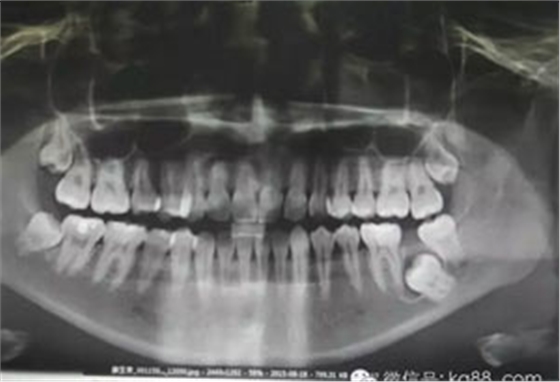

圖1.術(shù)前患者的全景片影像檢查情況:37未萌出,牙冠周圍有囊性陰影,牙根接近下頜骨皮質(zhì)骨邊緣。